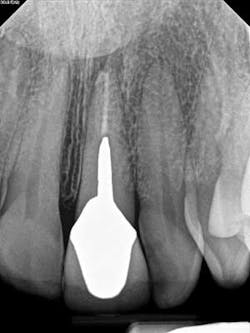

A 60-year-old male patient presented with a buccal swelling in the maxillary left anterior. Clinically the patient had a three-unit bridge connecting Nos. 7–9 (figure 1). The patient was happy with the esthetics and wanted to save his natural dentition. The recommendation was made to take a narrow-field CBCT scan to evaluate No. 7 in three dimensions. The CBCT scan showed that the apical disease had led to root resorption at the apical third of tooth No. 7 on the distal root surface (figure 2). This was invaluable information that allowed me to make the best approach to the root surface while keeping the osteotomy as small as possible. It also allowed me to have a three-dimensional view of No. 7 before even beginning the surgery, which helped to aid in proper root resection to conserve as much sound tooth structure as possible.